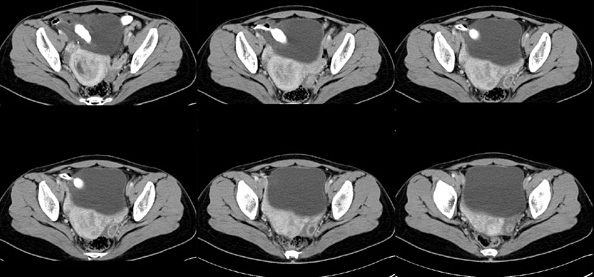

女性,28岁,停经3月,腹部膨隆1月,产前检查发现腹部占位

{肿块中心ct值27hu,增强后,动脉期、门脉期均无明显强化)

患者手术病理:腹腔囊性淋巴管瘤,象这样充满整个腹腔的的确很少见